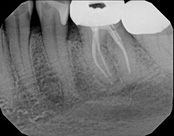

The patient presented with mild pain, a cavity, and a broken filling was evident. After performing diagnostic testing, the diagnosis was: irreversible pulpitis, symptomatic periradicular periodontitis. Root canal therapy was done and the tooth healed well and is still functioning.